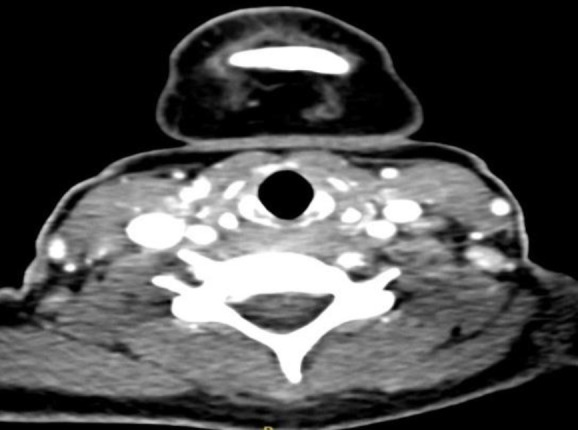

Case report: We presented a case of Kikuchi-Fujimoto disease in a 29-year-old female mimicking sepsis after a COVID-19 infection. Clinical examination revealed stable vitals and multiple diffuse non-tender bilateral cervical and axillary lymph adenopathy with hepatosplenomegaly. The patient's blood parameters showed leukopenia, raised erythrocyte sedimentation rate, lactate dehydrogenase, microcytic hypochromic anemia with normal renal and liver function tests. The patient was treated with broad spectrum intravenous antibiotics and subcutaneous neupogen with a clinical suspicion of sepsis. The patient then underwent a CT scan which validated the clinical findings. Although the fever subsided, a persistent cervical lymphadenopathy was observed and the biopsy confirmed it to be necrotising lymph adenitis secondary to Kikuchi-Fujimoto disease. This patient has been regularly monitored and has shown resolution of cervical lymphadenopathy.